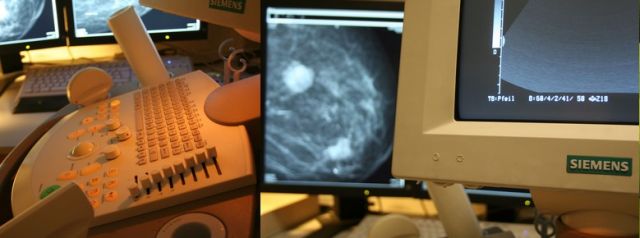

Ultraschall / Sonographie

In unserer Praxis werden folgende Ultraschalluntersuchungen angeboten:

- Brustdrüse (Mamma)